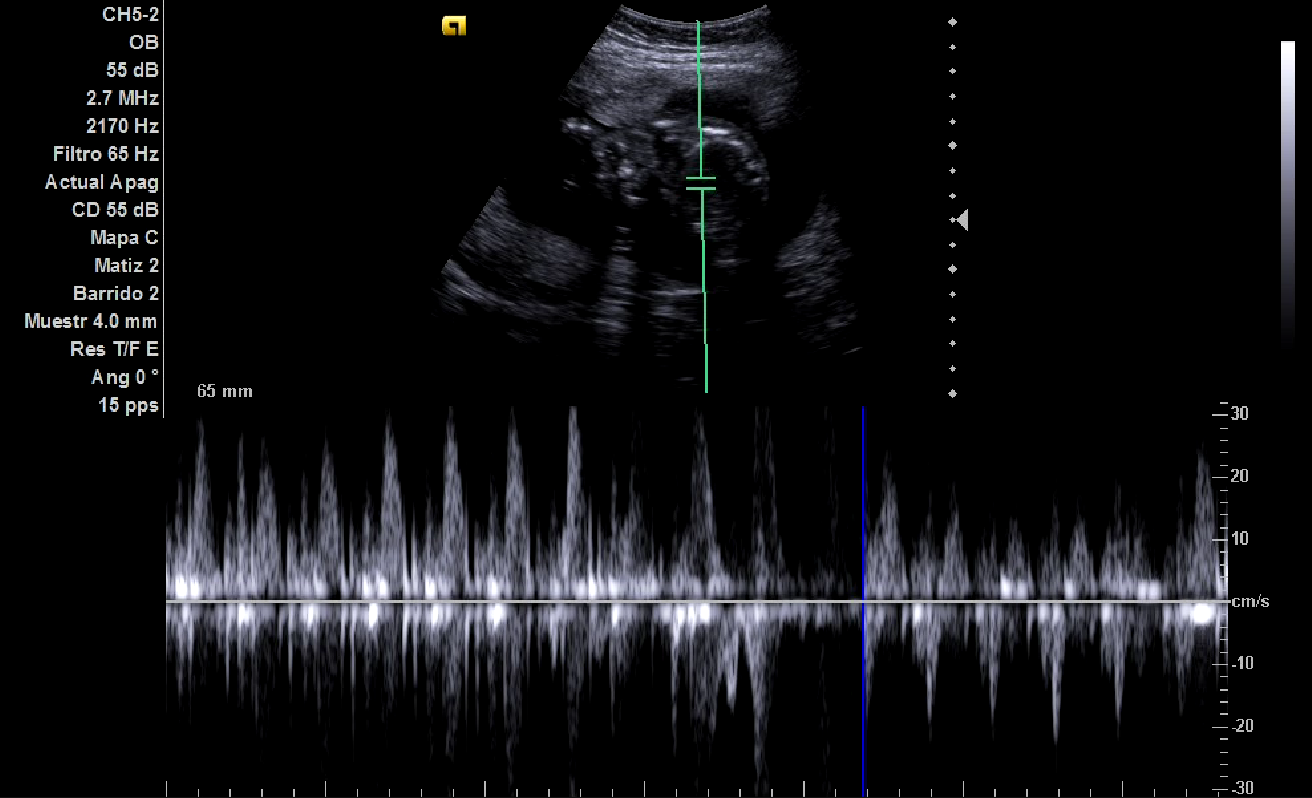

Ecografía: posición fetal con cabeza hacia la izquierda, bolsa más profunda de líquido amniótico de 7 centímetros, actividad cardíaca fetal normal (imagen 3), placenta ubicada en posición anterior, feto único. Se realiza medición de perímetro cefálico y diámetro biparietal (imagen 1) usando software de ecógrafo, así como del perímetro abdominal (imagen 2), estimando una edad gestacional entre 19 semanas y 1 día (cefálico) y 20 semanas y 3 días (abdominal).